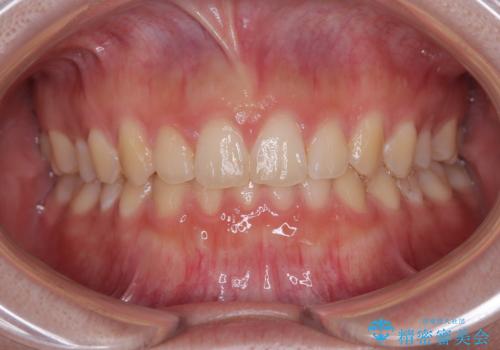

前歯のすきっ歯を治したい インビザラインによる矯正治療

一度インビザラインのマウスピースセットをお渡しすると1年以上来院されず、マウスピースを破損したり紛失したりすると来院されるというのんびりとしたペースで治療を行ったため、4年間という長期にわたる治療となりました。

最終的には隙間は全て閉じ、綺麗な仕上がりとなりました。